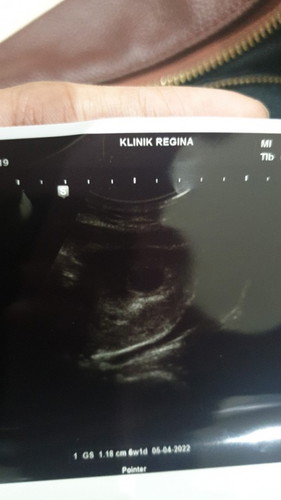

Usia 6 minggu kehamilan

Assalamualaikum bunda kandungan 6 minggu dan hasilnya masih kantung, itu wajar ngak ya bunda #seriusnanya ##bantusharing

Iya saya juga waktu usg 6w juga masih kantong dengan ukuran 2,37cm apa normal ya ?